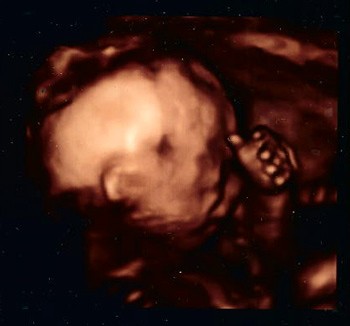

Moja kochana buźka :)

"Facet ale uparty jak baba i do tego akrobata" :) - to słowa lekarza, dopiero po ok 15 minutach USG pokazał siusiaka :)